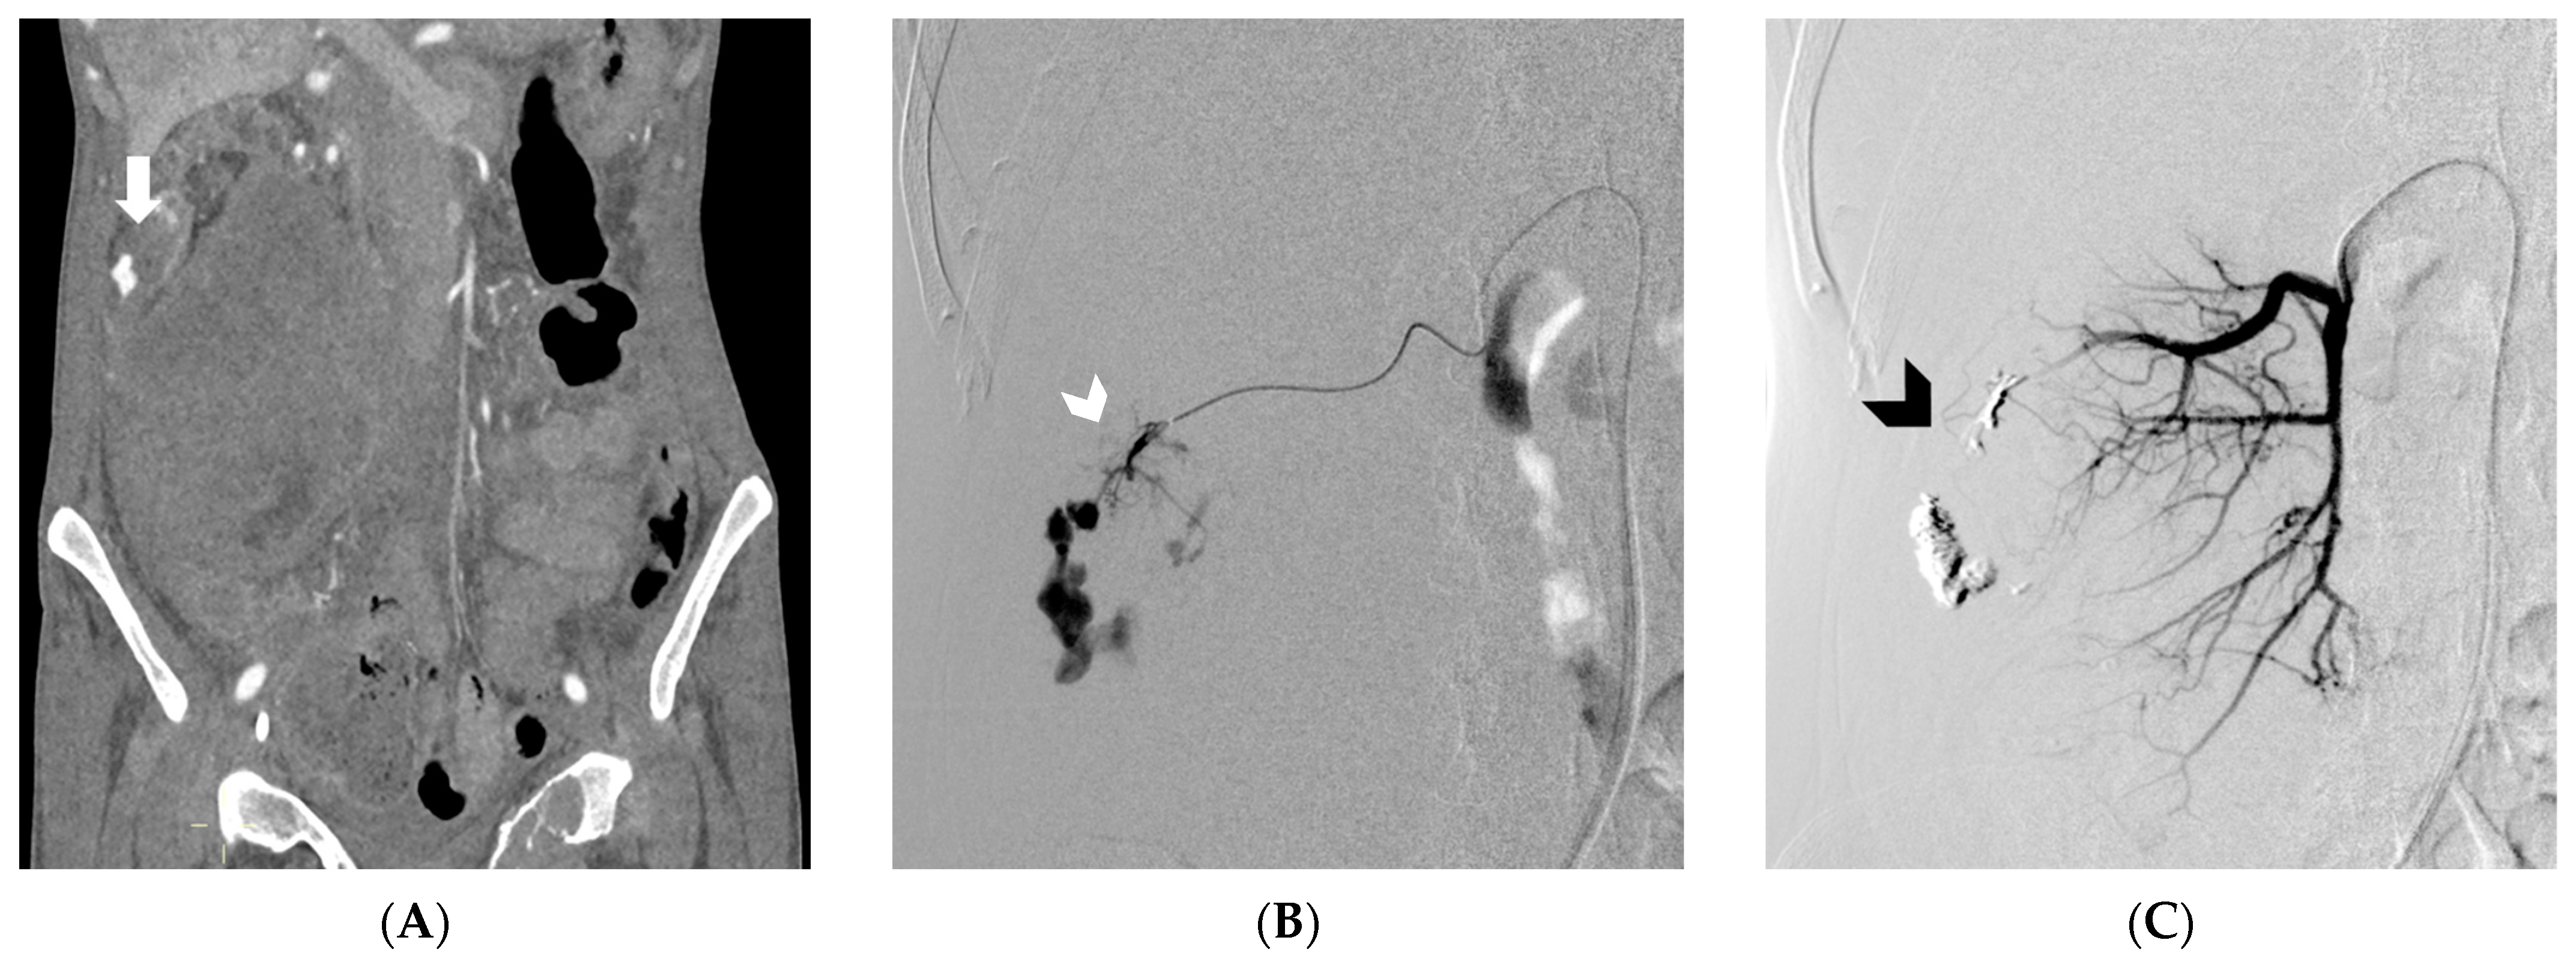

Figure 2. In Figure (A), Computed Tomography angiography reveals spontaneous retroperitoneal bleeding attributed to a ruptured pseudoaneurysm (indicated by the arrow) originating from a renal tumor. Figure (B) shows digital subtraction angiography, which confirms the presence of a ruptured pseudoaneurysm arising from a feeding artery of the tumor (white arrowhead). Lastly, Figure (C) displays digital subtraction angiography, illustrating the successful embolization achieved using an Ethylene-Vinyl Alcohol copolymer cast (indicated by the black arrowhead). (From Minici et al. doi: 10.3390/medicina59040710, by MDPI, Basel, Switzerland, licensed under CC BY 4.0).